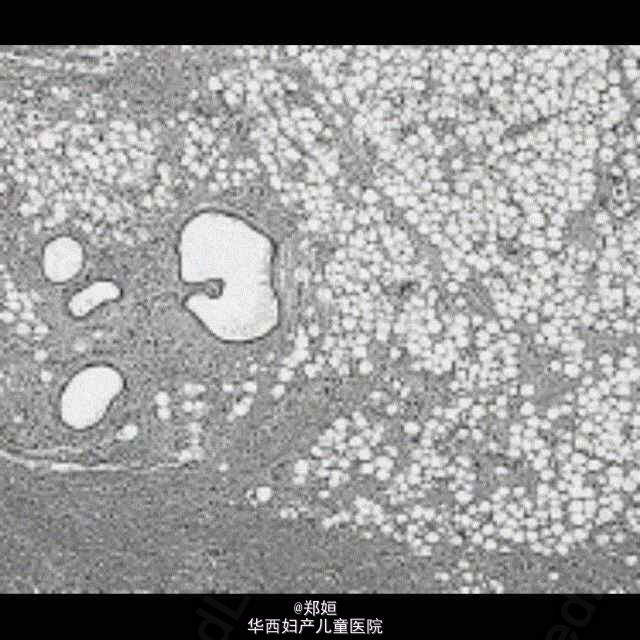

50岁女性,外阴无疼痛性膨胀数月

查体后初步诊断为外阴血管粘液瘤

初步诊断为外阴血管粘液瘤 行肿瘤的局部切除

恢复良好,无复发 外阴血管肌纤维母细胞瘤是发生于外阴、会阴及腹股沟区的具有一定临床病理特征的浅表软组织肿瘤。较为少见。血管肌纤维母细胞瘤发病比较隐匿,常常是患者无意中发现外阴肿物,病程数月至数年,一般无疼痛。肿物大多位于大阴唇和外阴区,肿瘤边界清楚。本病很少能在术前做出明确诊断,肿物局部切除可治愈,一般不复发。